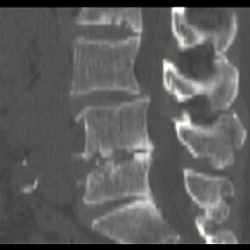

15.04.2011 - 19:31

2005 г. Стационар. Б-ной 78 л. Боли в пояснице. Диагноз клинициста - туберкулёз. Внезапная смерть пациента. Патоморфолог отвергает туберкулез. Рентгенологическая документация прилагается. Других...